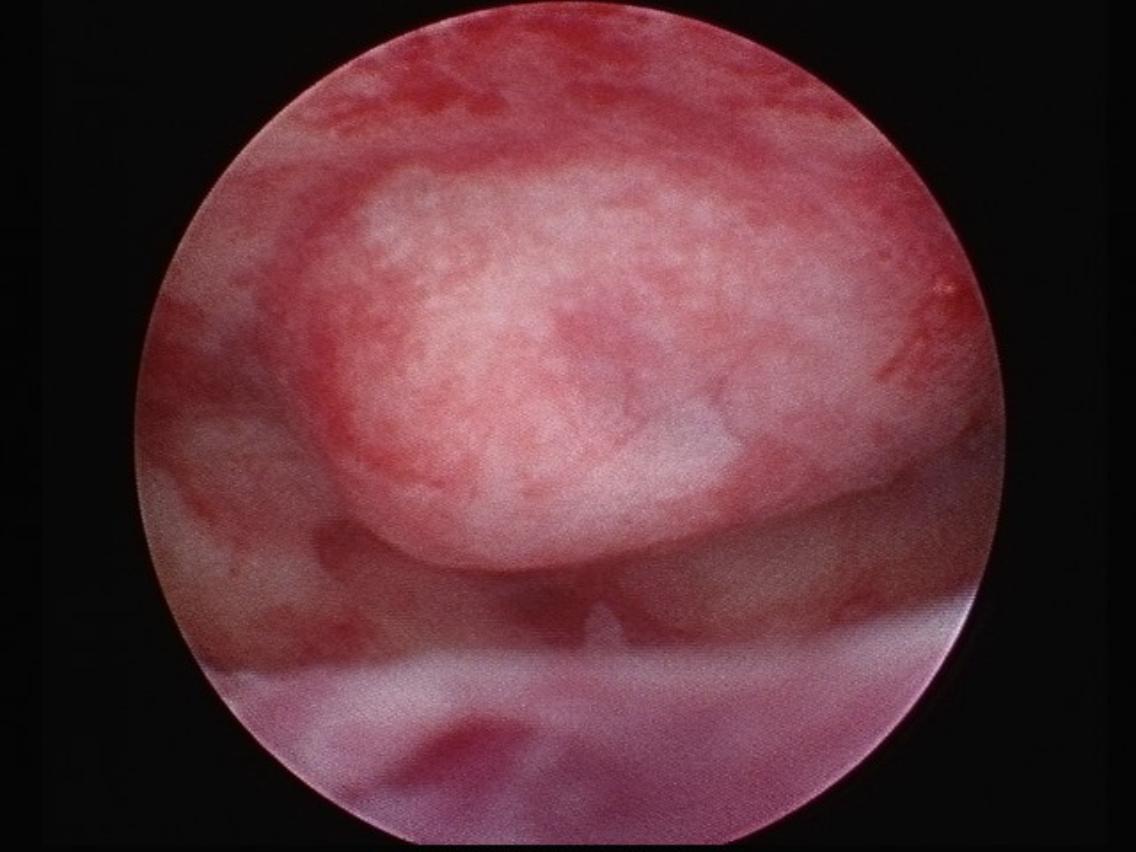

粘膜下肌瘤示意圖。(圖片來源/傑生婦科內視鏡微無創中心院長曾宇泰)